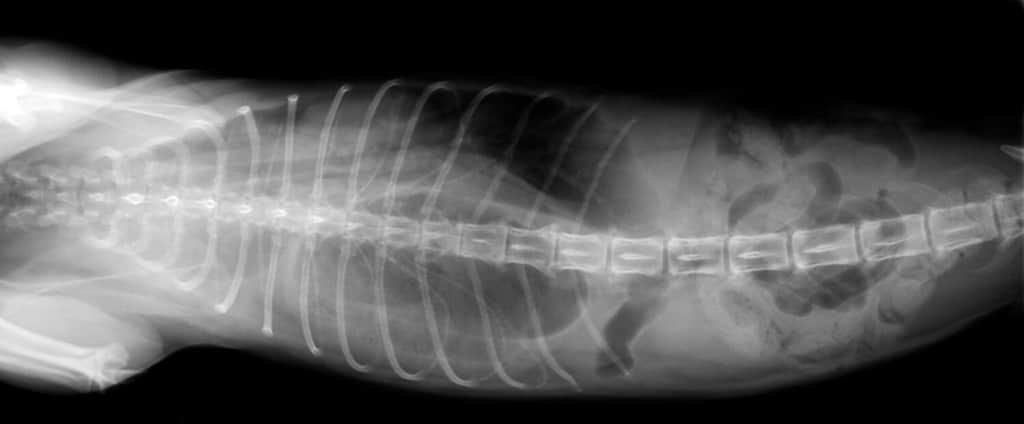

Ernia diaframmatica

©Trevor Reeves/Shutterstock.com

Le ernie diaframmatiche si trovano nel diaframma di un cane, che è un muscolo situato tra il torace e l’addome. I cani possono nascere con un’ernia diaframmatica o può svilupparsi a causa di un trauma.

Il rischio maggiore di queste ernie è che gli organi addominali possano entrare nel torace, rendendo difficile la respirazione del cane.

Per questo motivo, è una condizione emergente che in genere richiede un intervento chirurgico. Se il tuo cane ha altre ferite dovute a un trauma, potrebbe essere ricoverato in ospedale mentre il veterinario attende che si stabilizzino abbastanza per un intervento chirurgico.

La prognosi di un cane è buona se riesce a sopravvivere nelle prime 48 ore dopo l’intervento, ma nel complesso questa è una diagnosi critica.

Per confermare la diagnosi di un’ernia, eseguiranno quindi radiografie o un’ecografia.